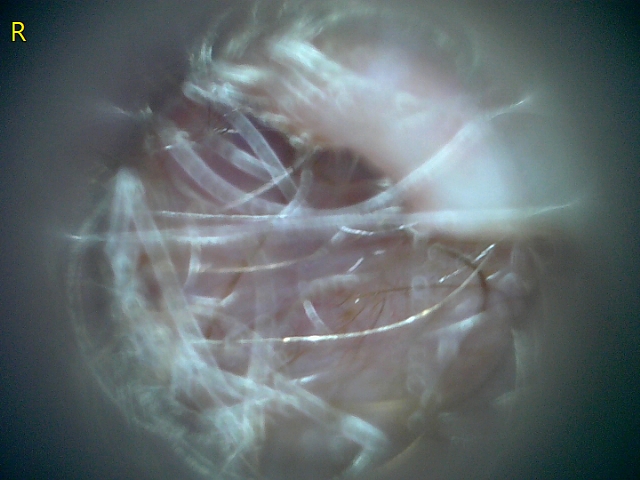

23207 177217 Into CNS 000010